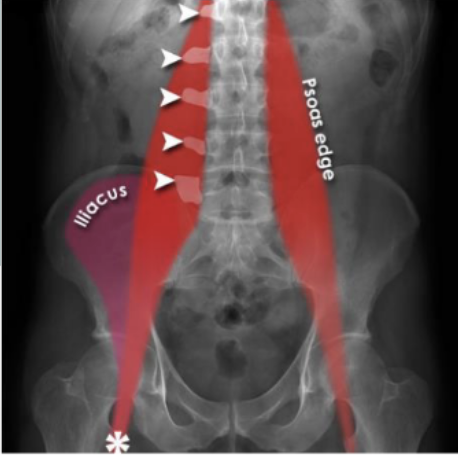

Identify Psoas muscles, lumbar vertebrae, femur, illiacus

yes